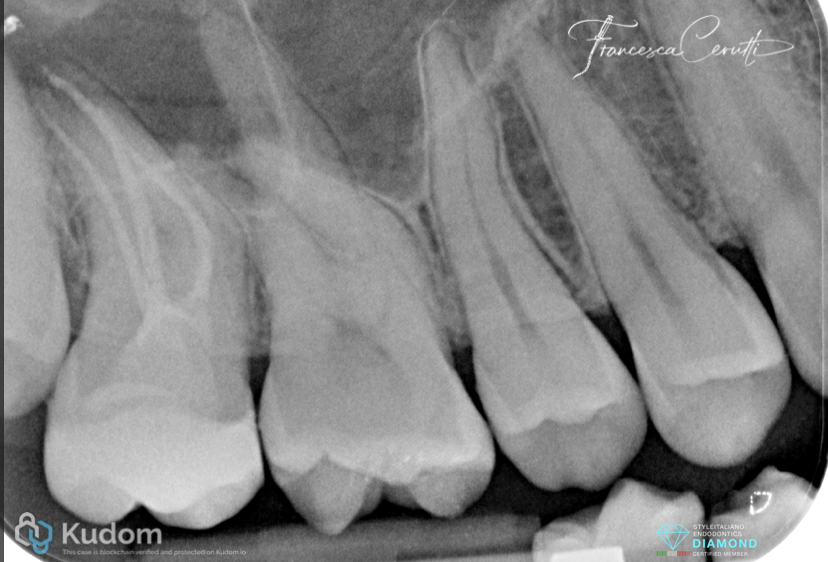

Fig. 13

Post operative X-ray

Fig. 14

Follow up X-ray